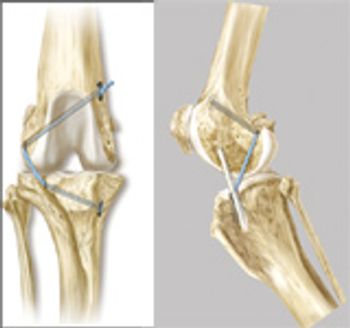

Treatment of cranial cruciate ligament deficiency is the most common surgical procedure performed in veterinary orthopedics.

Cranial cruciate ligament (CrCL) rupture is the most common cause of hindlimb lameness in dogs.